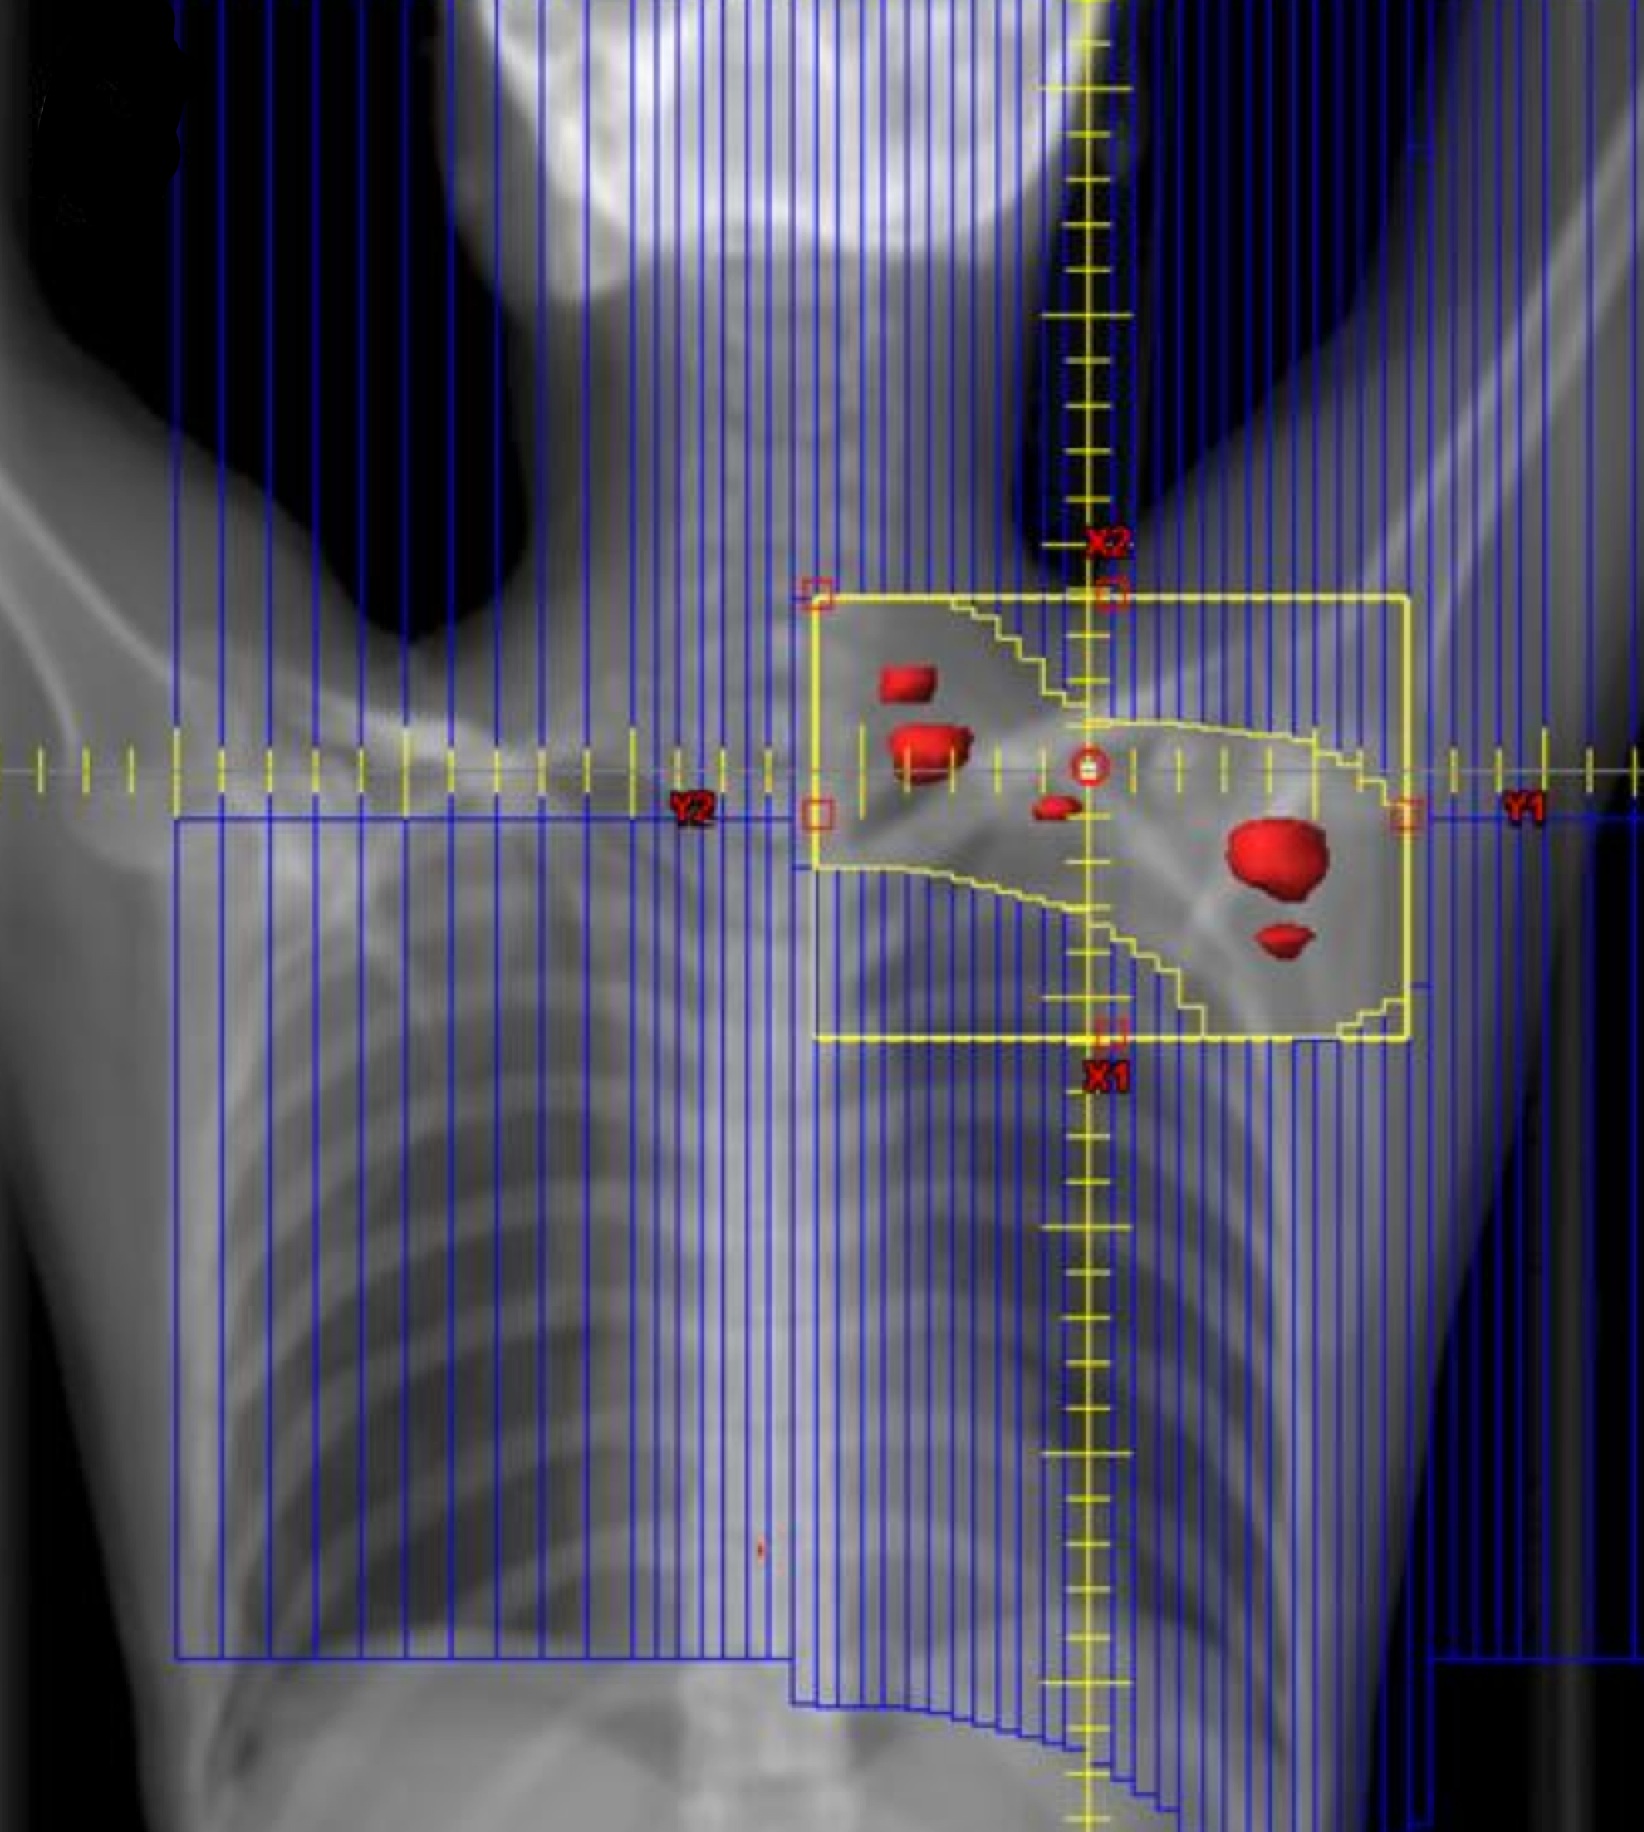

ISRT is most commonly recommended now as the most appropriate treatment field (Yaholom). Determining the optimum involved site definition may require incorporation of PET and MRI as well as pre-treatment and treatment planning CT to define the optimum volume.

Involved Site Radiation Field

• includes original extent of disease with margins to account for imaging limitations and disease specifics

• Recommended, based on GTV → CTV → PTV

• CTV=pre-chemotherapy extent of disease based on PET-CT

• CTV adjusted to exclude uninvolved normal tissues such as lung after tumor shrinkage

• CTV expanded to incorporate imaging/disease uncertainties

ISRT targets the site of the originally involved lymph nodes. This volume encompasses the pre-chemotherapy/pre-operative volumes. The fields are modified to spare adjacent uninvolved organs (lungs, bone, muscle, kidney), when the disease shrinks following chemotherapy. Concerns about the precise accuracy and localization of pre-treatment disease may lead to an expansion of the CTV based on clinical judgement. For NLPHL where radiotherapy is the sole modality treatment, a larger field should be considered.